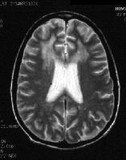

• Aids dementia complex на NMR слици као један од симптома полне болести СИДЕ